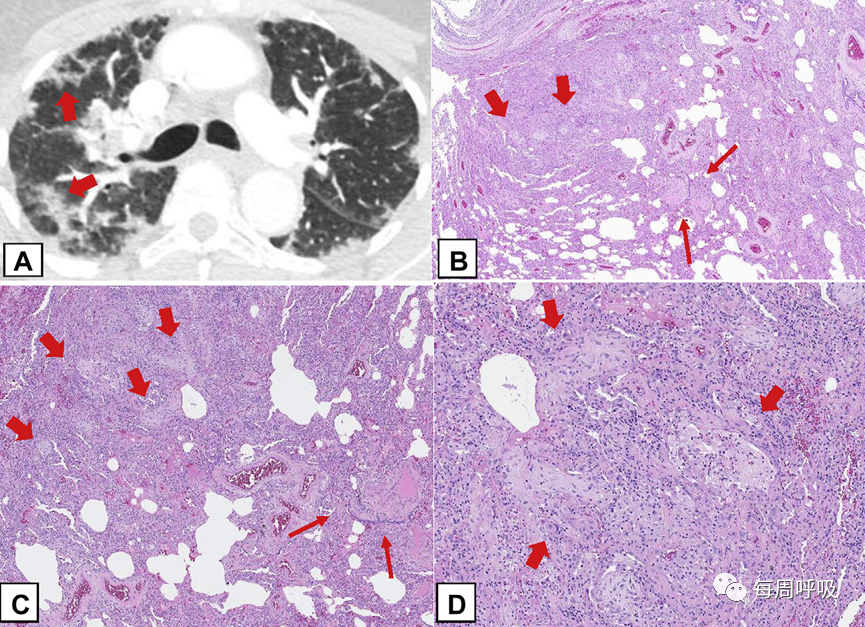

低倍镜下,OPP呈斑片状,与结节样机化区域相邻的肺相对正常(图20)。机化性纤维化包括腔内疏松结缔组织息肉样塞子,突出到远端气腔。肺泡间隙和肺泡管通常受影响最大,细支气管受影响较小(图20A, 20B),在某些情况下,活检标本未见细支气管受累。OPP结节可以位于细支气管周。少见的是,它们可能出现在小叶周围,与CT扫描所见的小叶周围型相对应(图21)。所有的结缔组织似乎都是大致相同时期,肺的结构完整。来自COP或SOP患者的外科活检标本通常表现为OPP的多中心病灶,在FOP中,组织学外观与COP或SOP相似,但它由一个孤立的局限性结节组成(图20C, 20D)。间质纤维化不明显或不存在。没有看到蜂窝状改变。由于远端气道闭塞,可能出现内源性类脂性肺炎,由充满脂质的泡沫巨噬细胞在肺泡积聚。肺泡纤维蛋白渗出物可能存在,但通常是局灶性的。间质性慢性炎症通常为轻度至中度。2型肺细胞增生通常不明显。

图20 机化性肺炎(OP)的组织学表现(OPP)。在这个多灶性肺受累的隐源性OP病例中,低倍镜组织学图像(A)显示斑片状疏松结缔组织形成的息肉样腔内栓子(粗箭头)区域,突出到远端气道。邻近的肺实质相对正常(细箭头)。B,图示肺泡腔和肺泡管内可见息肉样栓子(粗箭头),但细支气管受累很少(细箭头)。结缔组织时期相同,肺泡结构保留。C,本例局灶性OP,如(a)和(B)所示,可见由OPP组成的结节性病变,周围是相对正常的肺(细箭头)。D,病变由远端气腔疏松结缔组织的息肉样栓子组成(粗箭头)。

图21 小叶周围机化性肺炎(OPP)。A,在上叶水平获得的轴位CT扫描图像显示右肺周边的小叶周围阴影(箭头)。B,在这个外科肺活检标本中,OPP的病变(粗箭头)在组织学上也位于小叶的外围,远离小叶中心的细支气管(细箭头)。C,中倍镜突出显示小叶边缘的OPP病灶(粗箭头),远离小叶中心的细支气管(细箭头)。D,高倍镜显示疏松结缔组织的息肉样栓子突出到远端气腔(粗箭头)。